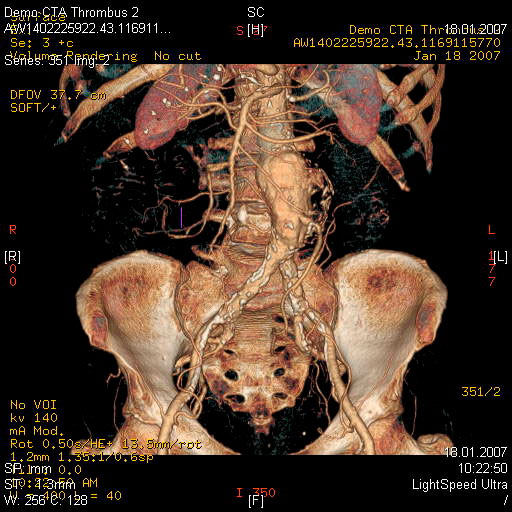

МСКТ высоко чувствительна в диагностике атеросклеротических кальцинированных, ,,мягких,, бляшек. В большинстве клиник метод МСКТ стал основным методом диагностики заболеваний сосудов сонных артерий, грудной, бюшной аорты, периферических пртерий.

- диагностика сосудистых заболеваний (аневризмы, стенозы, мальформации, аномалии развития)

- Выявление венозного тромбоза

Эмболии лкгочной артерии, источником которых обычно являются тромбы в венах таза и нижних конечностей являются грозным и относительно частым осложнением особенно у лежачих больных и после операции. Данные при рентгенографии неспецифичны. Без инфаркта может определяться приподнятие купола диафрагмы и сужение теней сосудов к периферии. Возможности МСКТ в диагностике ТЭЛА в ряде случаев позволяют отказаться от проведения инвазивной ангиографии.